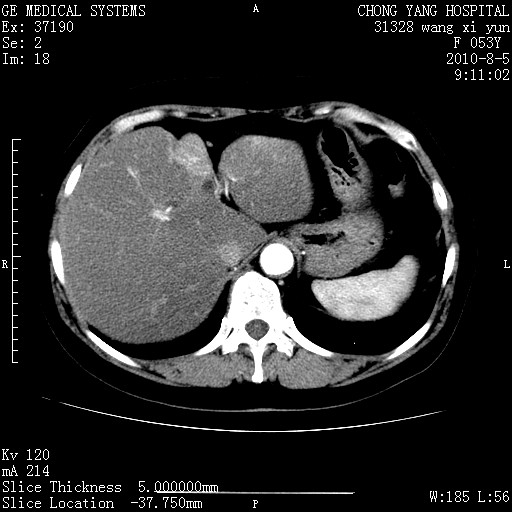

胆管细胞ca?

1)考虑肝左叶胆管细胞癌。2)脂肪肝。

支持胆管细胞ca。